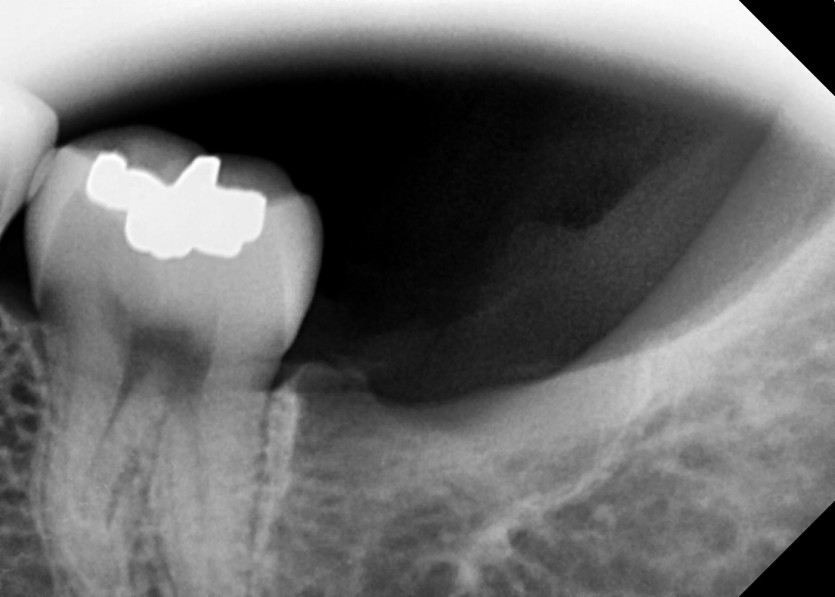

#38,48 사랑니 발치

구강 외과 전문의가 당일 발치했습니다.